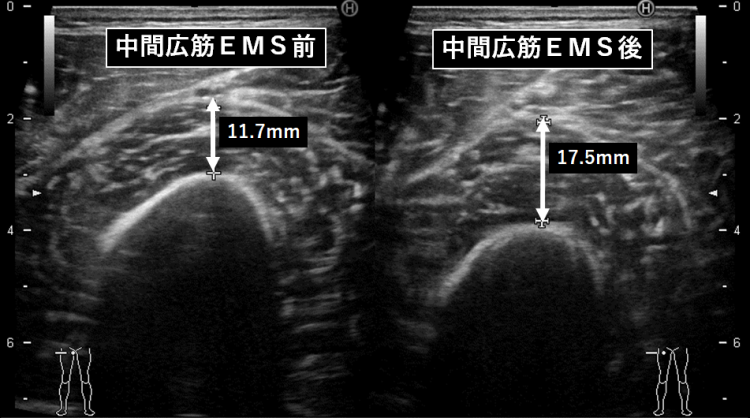

中間広筋に対する効果

(2022年1月 筋電メディカル®EMS試作機にて測定)

中間広筋とは、大腿四頭筋を構成する筋肉の一つで、中間広筋は大腿部前面の深層にある強力な筋肉で直接触れることはできない。

中間広筋は他の広筋群とともに膝関節の伸展動作に作用する。

中間広筋は、大腿四頭筋のなかで最も深部にあるため、EMSを用いて外部から電気刺激を用いても、筋収縮を誘発することは大変困難であった。

「筋電メディカル®EMS」の刺激が中間広筋に到達していれば、刺激中は筋収縮が誘発され、その結果、筋肉の厚みが増加することが期待できる。

このことを確認するため、「筋電メディカル®EMS」を用い、腹部および膝上に電極を装着して電気刺激を行った。

超音波測定により刺激中の筋の厚み変化を測定したところ、刺激前は11.7mmだった筋厚は、刺激中、17.5mmになっていることが確認できた。

このことは、「筋電メディカル®EMS」の電気刺激は、体深部にまで到達可能であり、中間広筋のような体深部の筋収縮の誘発をも可能であることを示唆している。